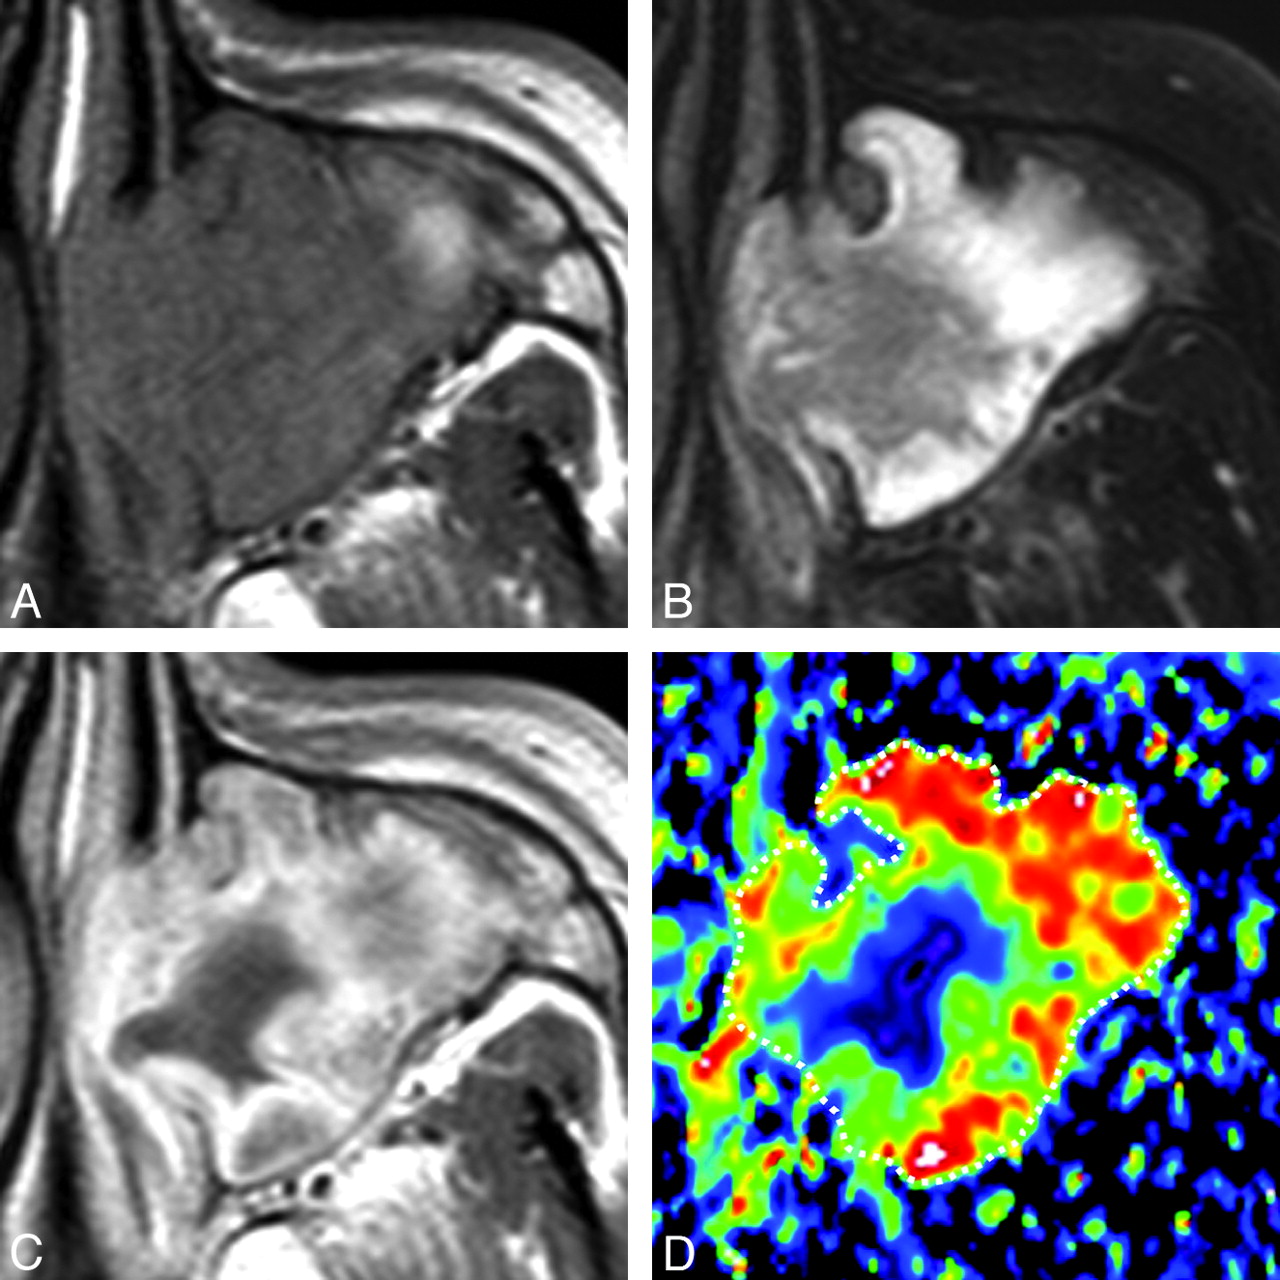

A 65-year-old man with SCC. A, Axial T1-weighted MR image (TR/TE = 500/15 ms) shows tumor with homogeneous signal intensity occupying the right maxillary sinus and extending into the surrounding bony structures. B, Axial FS (SPAIR) T2-weighted MR image (TR/TE = 6385/80 ms) shows tumor with heterogeneous signal intensity. C, Axial contrast-enhanced T1-weighted MR image (TR/TE = 500/15 ms) shows tumor with peripheral enhancement. D, Axial color ADC map shows tumor with a low ADC. Overall ADC = 0.8 × 10−3 mm2/s. Areas with extremely low, low, intermediate, and high ADCs occupy 17%, 78%, 5%, and 0%, respectively, of the tumor.